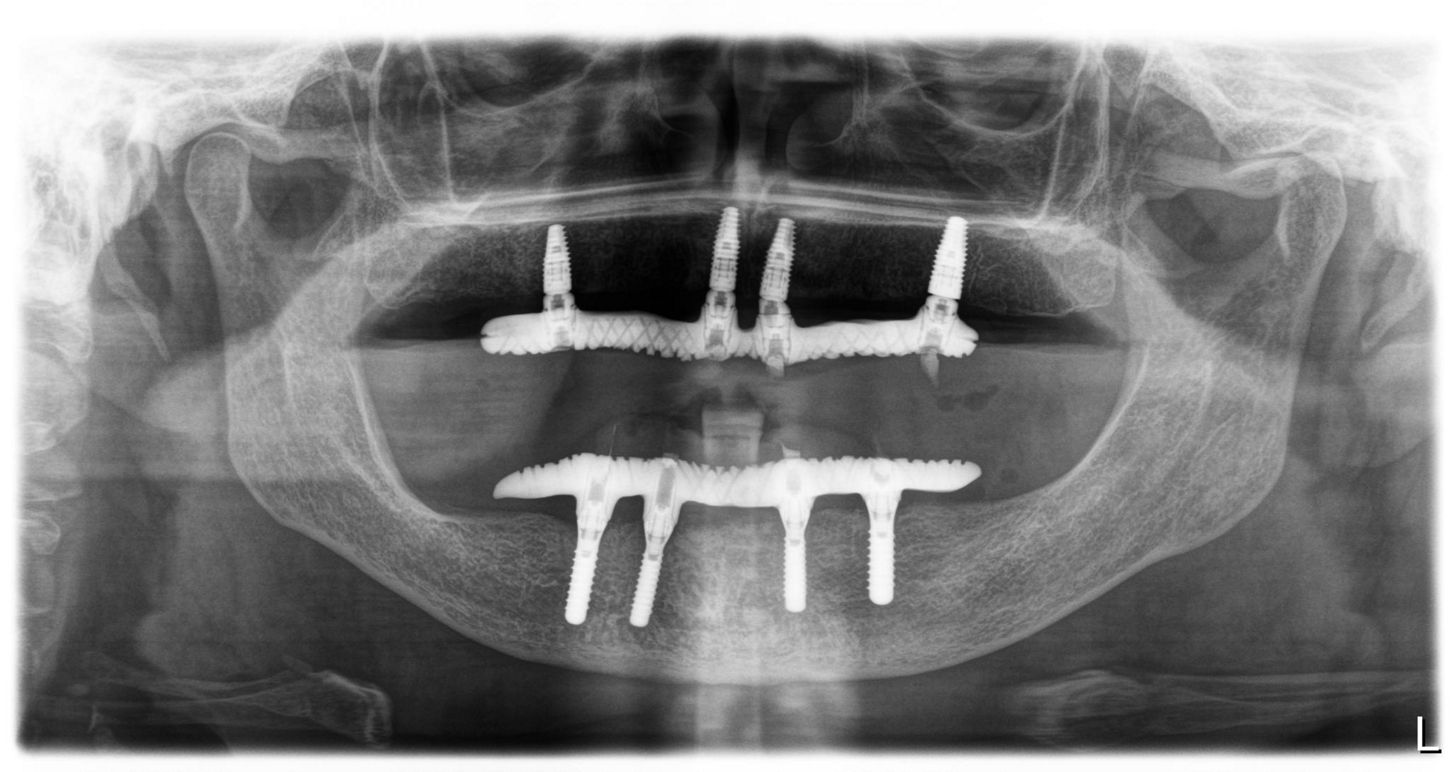

Иллюстрация 14

Через 4 месяца установлены постоянные протезы на верхней и нижней челюстях с опорой на дентальные имплантаты.

Окклюзионные винты, фиксирующие условно-съемные протезы затянуты на усилие 15 Н/см на верхней челюсти.

Шахты закрыты тефлоновой лентой и композитным материалом Gradia AO2 (Илл. 14-20).

Критерием выбора имплантата TL на нижней челюсти является пародонтит в анамнезе, а также избыточное количество мягких тканей, более 4 мм.  Дизайн имплантата TL представлен фрезерованной шейкой диаметром 4.8 мм, которая позволяет поддерживать конструкцию плечом шейки, обеспечивая надежную опору и снижение нагрузки на абатмент и фиксирующий винт.

Критерием выбора имплантатов BLT на верхней челюсти является пористая кость и необходимость стабилизации имплантата для обеспечения немедленной нагрузки за счет модификации хирургического протокола. Возможность использовать угловые решения с использованием абатментов SRA (угловые и прямые).